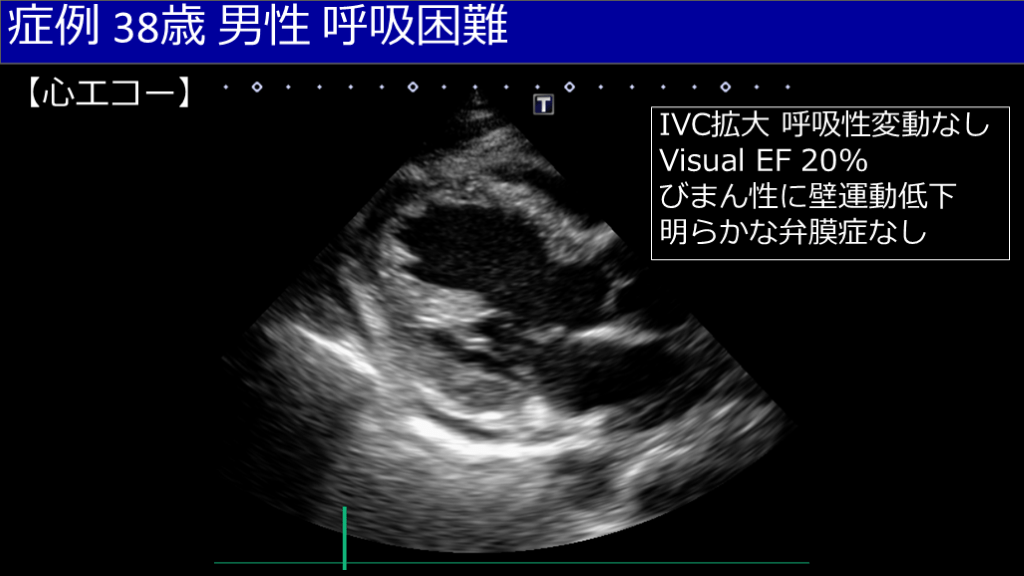

【心エコー】 症例 38歳 男性 呼吸困難 IVC拡大 呼吸性変動なし Visual EF 20% びまん性に壁運動低下 明らかな弁膜症なし

症例 38歳 男性 呼吸困難 【心エコー】